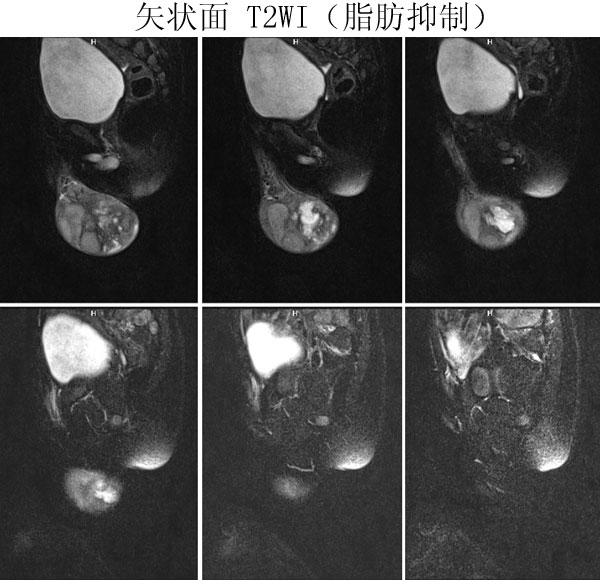

(广东同江医院的病例)男,2岁。左侧睾丸肿大3月,开始发现时红枣大,逐渐增大,现鸡蛋大小,表面光滑,无压痛,质地中等。

病理诊断 :(左侧)

睾丸胚胎性横纹肌肉瘤

,瘤组织局部浸润附睾组织,精索残端组织内未见瘤组织浸润。